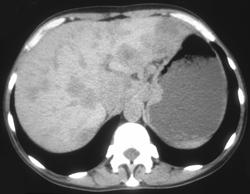

Gastric Leiomyosarcoma